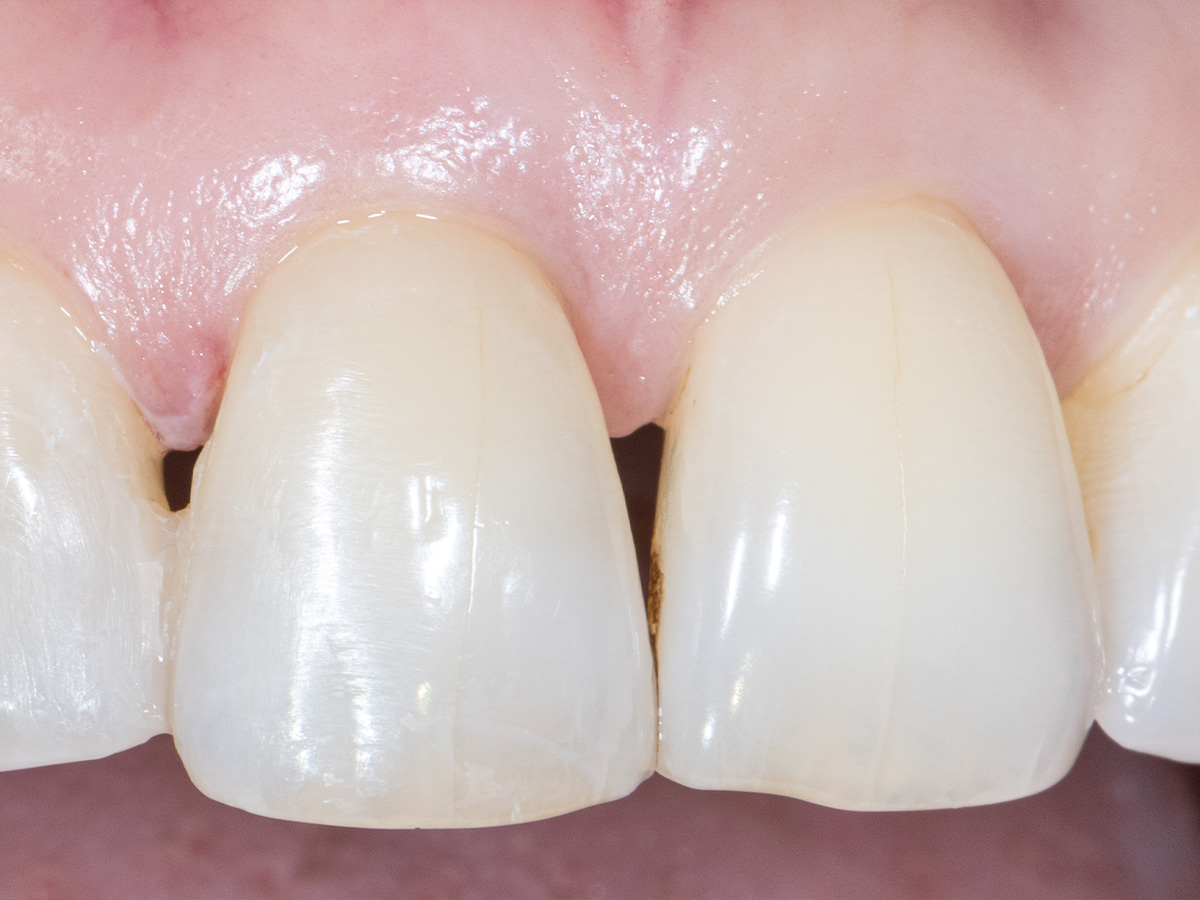

Die klinische Untersuchung nach sechs Monaten zeigt einen parodontal gesunden Zustand, keine Gingivarezession und keine Narbenbildung, da Oberflächeninzisionen auf der bukkalen Seite vollständig vermieden wurden

Das finale Bild nach Verschluss des Interdentalraumes mittels direkter Kompositrestaurationen zeigt ein ästhetisch ansprechendes Ergebnis.